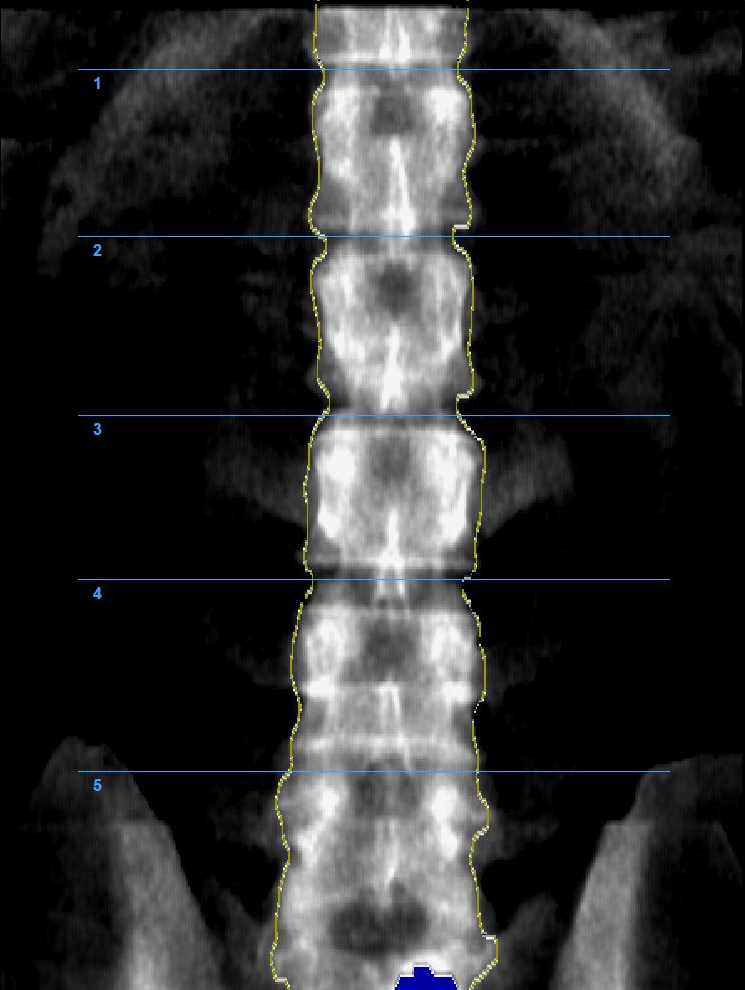

Денситометр Medikors InAlyzer-AIR оснащено 64-канальным двухэнергетическим рентгеновским датчиком, основанным на технологии веерных лучей, и позволяет получать 64 ряда данных за одно рентгеновское обследование, обеспечивая получение данных более высокого разрешения за более короткий период времени по сравнению с системами, основанными на технологии остронаправленных лучей и позволяющими получать только 1 ряд данных за одно рентгеновское обследование.

Денситометр InAlyzer-AIR, разработанный компанией Medikors, использует технологию рентгеновского излучения. Он пропускает сфокусированный рентгеновский луч через анализируемый объект – кость. Измеряется степень поглощения рентгеновских лучей, и эта информация используется для расчёта плотности и состава. Эта технология позволяет неинвазивно измерять минеральную плотность костной ткани и может использоваться для точной и достоверной диагностики остеопороза или мониторинга эффективности лечения.

С помощью InAlyzer-AIR можно определить не только минеральную плотность костной ткани, но и процент жировой и мышечной ткани.